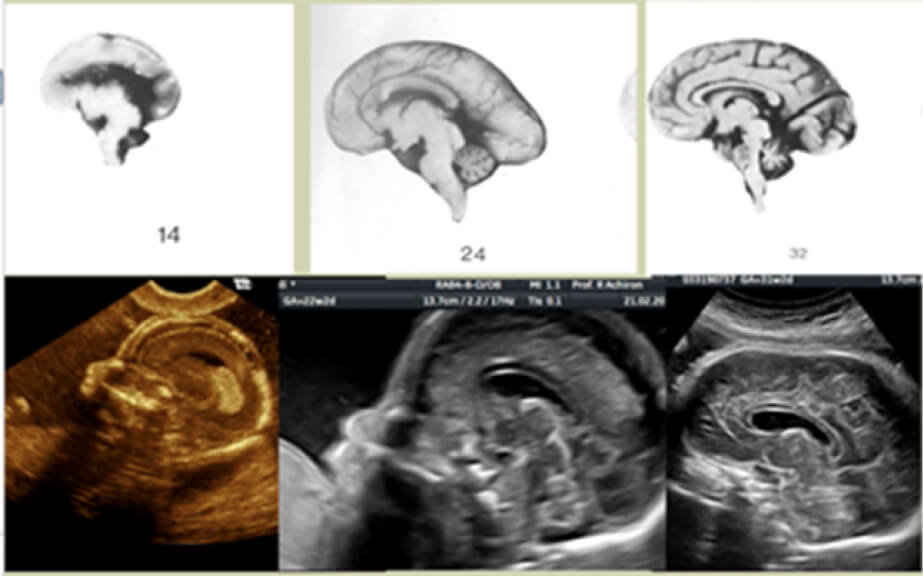

בשונה משאר מערכות ואיברי הגוף, מערכת העצבים והמוח מתפתחים ומשתנים לאורך כל שבועות ההיריון ועד לגיל שנתיים לאחר הלידה. מומים שונים במערכות אלה עלולים להתפתח בכל שלב בהריון.

בחינת התפתחות המוח ומערכת העצבים של העובר מתבצעת על-ידי רופא מומחה לאולטרסאונד וסקירת מערכות. הבדיקות השונות דורשות ידע מעמיק בתחום האמבריולוגיה ככלל ובהתפתחות המוח ומערכת העצבים בפרט. בנוסף, נדרשת גם היכרות מעמיקה ומומחיות ספציפית בכל הנוגע לסוגי המומים השונים הקיימים במוח ובמערכת העצבים ומועד ההופעה שלהם.

קליפת המוח מהווה את השכבה החיצונית של המוח הגדול. הקורטקס מורכב משכבות של חומר אפור, כלומר תאי עצב, האמונים על תפקוד תקין של המוח. קבוצת הפרעות זו כוללת מומים שונים הנבדלים אלה מאלה בהסתמנותם ובתוצאה הנוירולוגית.